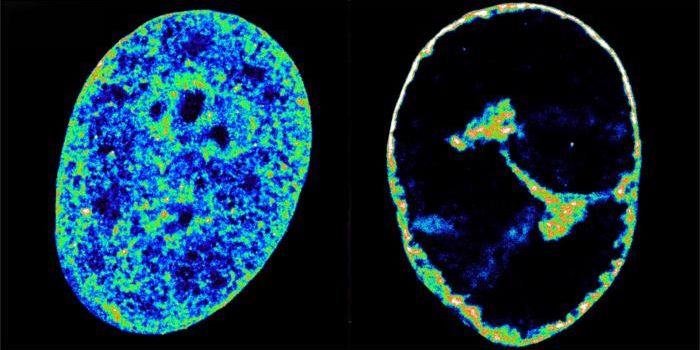

JUL 04, 2025Cannabis SciencesA Harvard University research team examined lung imaging to determine the association between cannabis consumption and h ...